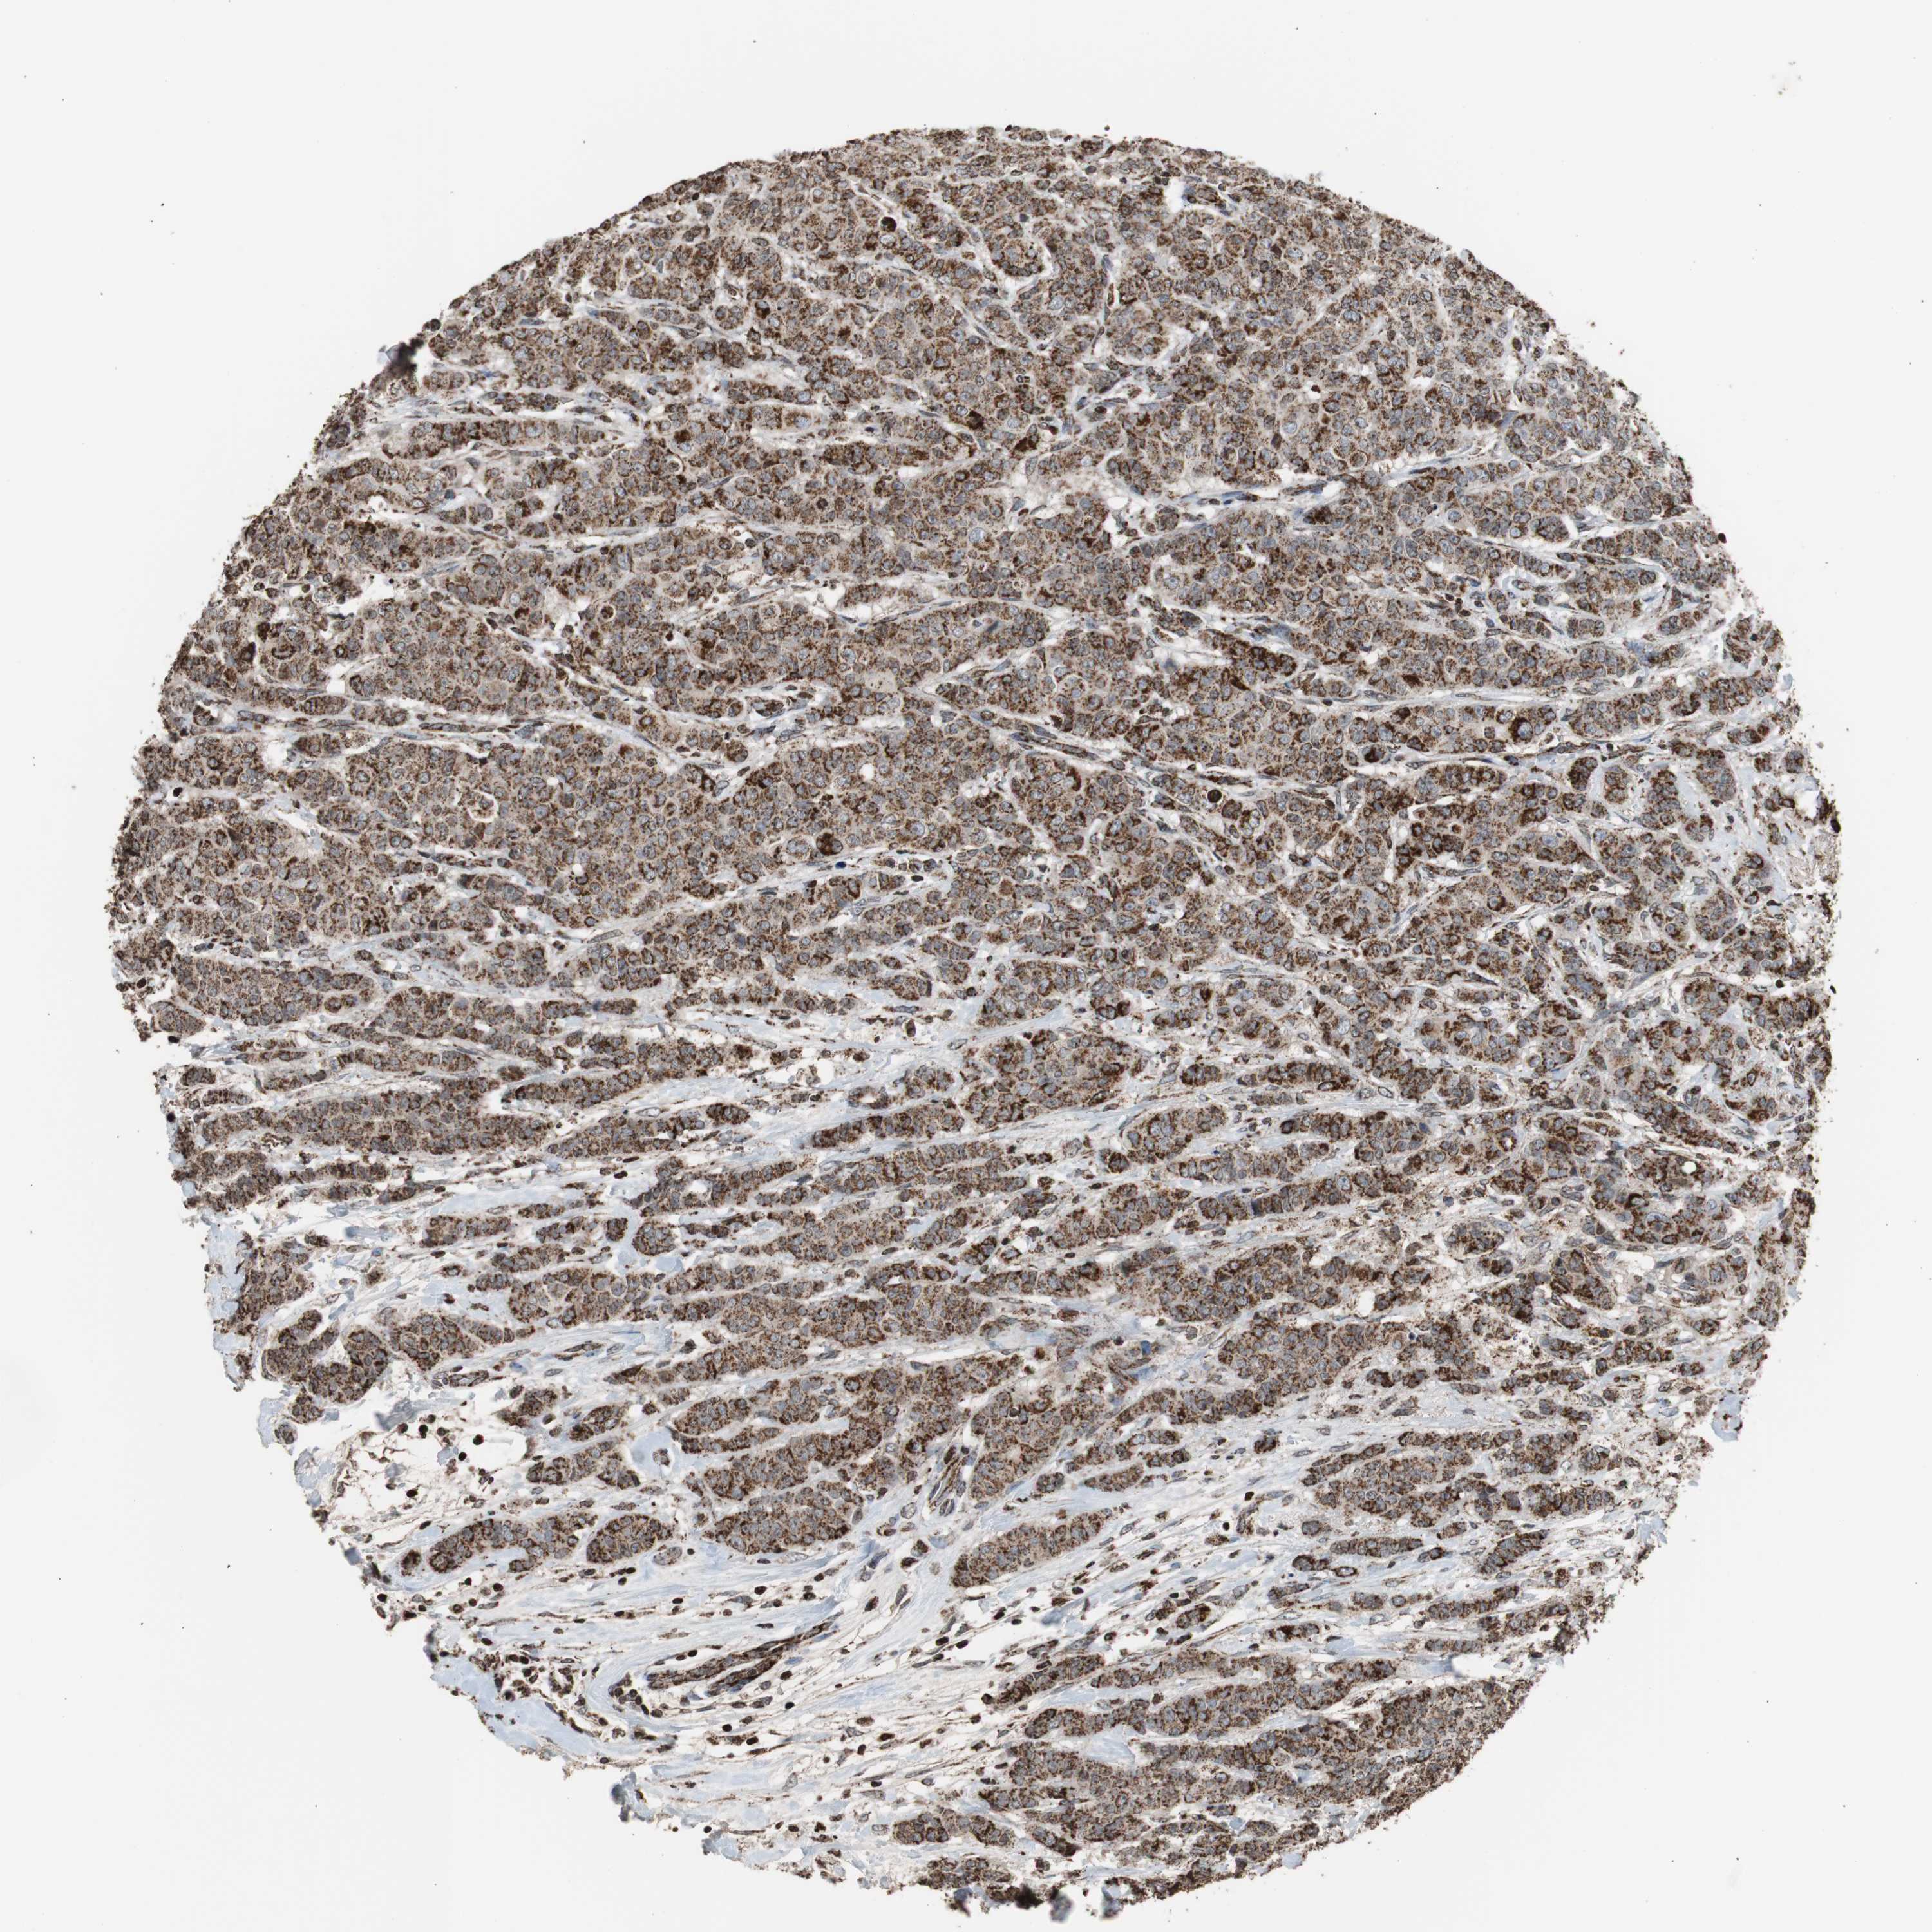

CANCER BREAST CANCER Show tissue menu

BRCA TCGA BRCA VALIDATION PROTEIN EXPRESSION